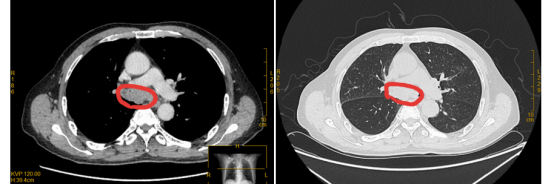

6月13日,陈伯开始接受免疫治疗,然而当天晚上病情却继续恶化,各项生命体征都出现衰退,似乎已经到了生命的尽头,这个时刻,家人、医务人员都没有放弃,医生更是熬更守夜地抢救,第二天病情终于迎来可喜变化,呼吸困难改善,病情一步一步地稳定、好转,经过2个疗程的治疗,他的呼吸通畅,生活已经可以自理了。CT复查结果显示,肺炎好了,双侧胸腔积液吸收,肿瘤正在逐步缩小,从原来的“鸡蛋”缩小成了蚕豆那么大。

治疗前:双侧主支气管几乎被肿瘤堵死

治疗2月后:肿瘤缩小,双侧主支气管恢复通畅